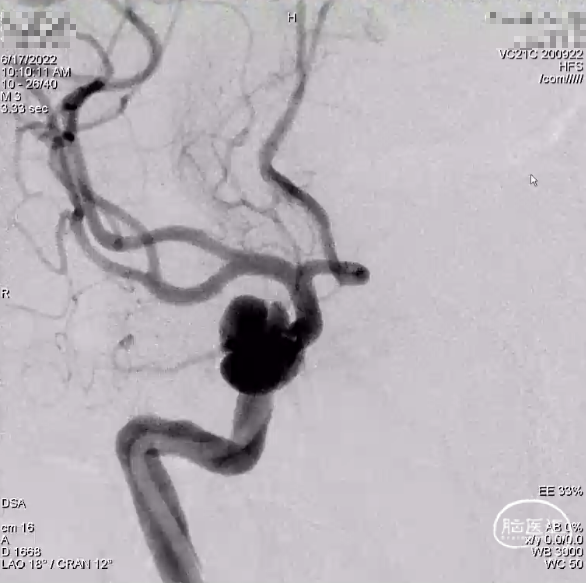

外院DSA

右侧颈内动脉眼动脉段-海绵窦段串联两枚动脉瘤,分别大小约:

① 8.8mm*5.9mm*5.2mm,瘤颈宽7.0mm;

② 6.8mm*4.3mm*3.6mm,瘤颈宽3.3mm。